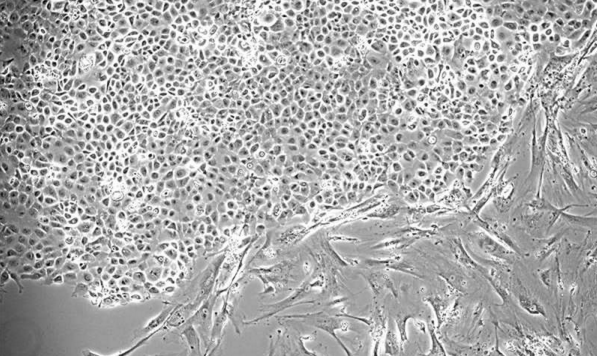

Stathopoulos 及其团队正在努力了解胸腔积液发生的原因,以期在未来推进治疗这种病症。在本研究中,科学家检查了他们从 KRAS 基因中具有恶性突变的胸腔积液获得的癌细胞。已知 KRAS 在各种恶性肿瘤的生长中起关键作用。

Stathopoulos 说:“我们能够显示这些细胞释放血液中的信使物质,这反过来会吸引免疫细胞,然后这些细胞通过脾脏漫游到胸膜腔,导致渗出。”